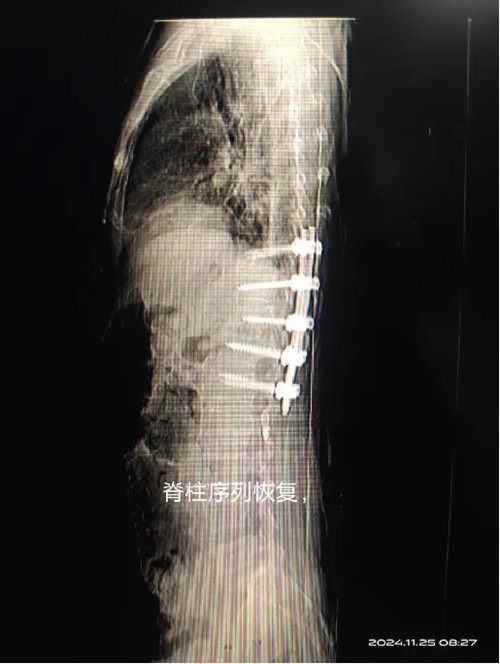

一切就绪后张长江主任,赵意华等医师为患者急诊实施手术,行椎体骨折复位钉棒固定,椎板减压植骨融合术,在超声刀辅助下手术很快结束,患者安全返回病房继续进一步治疗。及时的减压和融合固定,恢复脊柱序列,为脊髓的恢复创造稳定的环境和良好的条件。